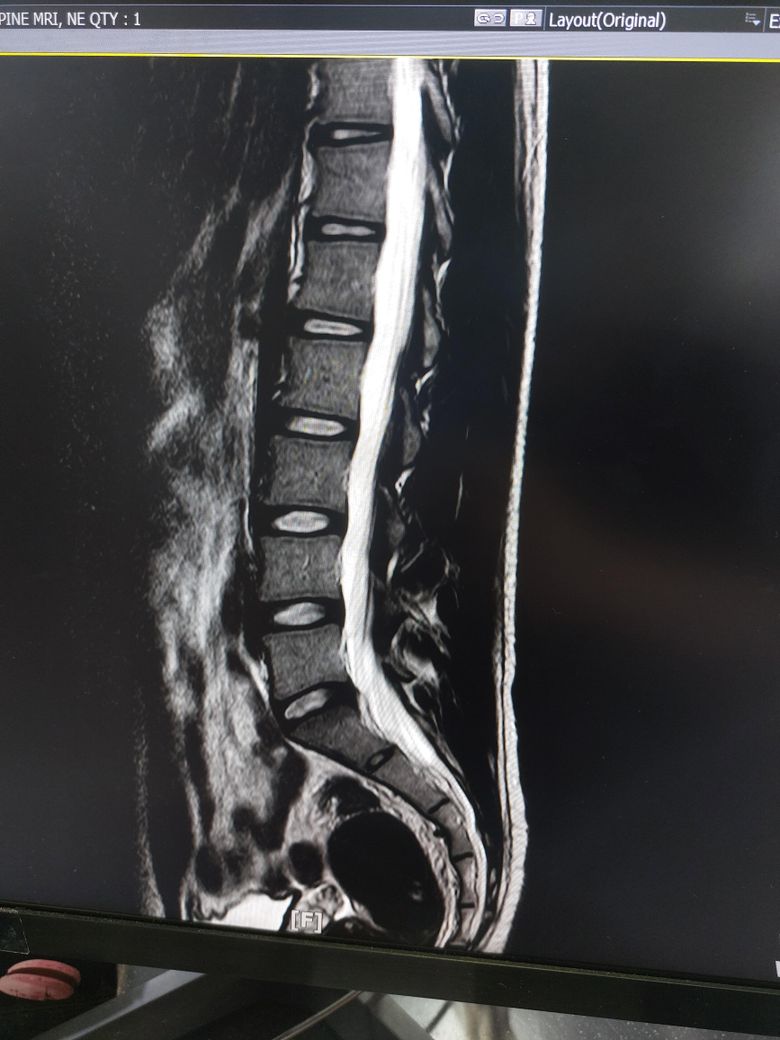

몇개월동안 요추부분이 뻣뻣하고 시큰거려서 (다리 증상은 없음) mri 촬영했는데

디스크 팽윤인가요 아니면 탈출인가요?

증상이 많이 심한가요?

추간판 팽윤입니다

MRI 영상만 가지고 말씀드린다면 심하지 않습니다.

• 올리신 사진 몇 장 가지고 정확한 상태 평가 및 판단을 내릴 수는 없지만 디스크 탈출 보다는 디스크 팽윤이 의심스런 MRI 소견으로 사료됩니다.